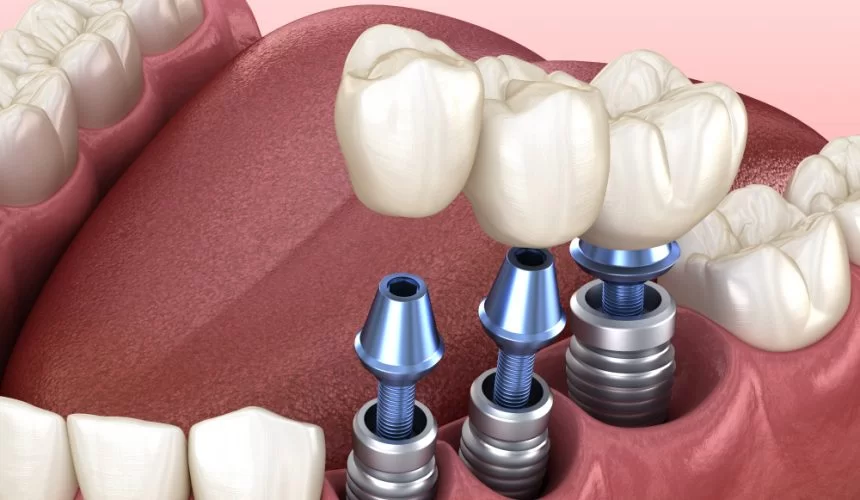

İmplant Tedavisi

Titanyumdan üretilen ve çene kemiğine yerleştirilen bu yapay kökler, üzerine yerleştirilecek porselen dişler için sağlam bir temel oluşturur. Dent360’ta, en güncel teknikler ve biyolojik uyumluluğu en yüksek malzemeler kullanılarak implant uygulamaları yapılmaktadır.

2. İmplant Tedavisinin Avantajları Nelerdir ve Herkes İçin Uygun mudur?

İmplant tedavisi, eksik dişler için modern tıbbın sunduğu en önemli çözümdür.

Doğal Görünüm ve Hissiyat: İmplantlar, çene kemiğine sabitlendiği için tıpkı doğal dişleriniz gibi görünür ve hissedilir. Çiğneme kuvvetini doğal dişler gibi kemiğe iletir.

Çene Kemiği Korunumu: Diş kaybından sonra kemik erimesi başlar. İmplant, çene kemiğini uyararak erimeyi durdurur ve yüz hatlarının çökmesini önler.

Komşu Dişlerin Korunması: Köprü tedavisinin aksine, implant uygulaması yapılırken komşu dişlerin kesilmesine veya aşındırılmasına gerek kalmaz.

Yüksek Başarı Oranı: Doğru uygulandığında ve ağız hijyenine dikkat edildiğinde, implantların başarı oranı oldukça yüksektir ve ömür boyu kullanım imkanı sunar.

Uygunluk: Genel olarak, yeterli çene kemiği hacmine sahip ve genel sağlık durumu cerrahi operasyon için uygun olan herkese uygulanabilir. Diyabet gibi sistemik hastalıkları olan hastalar, uzman diş hekimi tarafından detaylıca değerlendirilmelidir. Kemik yetersizliği durumlarında ise ileri cerrahi tekniklerle (kemik greftleme) destek sağlanabilir.